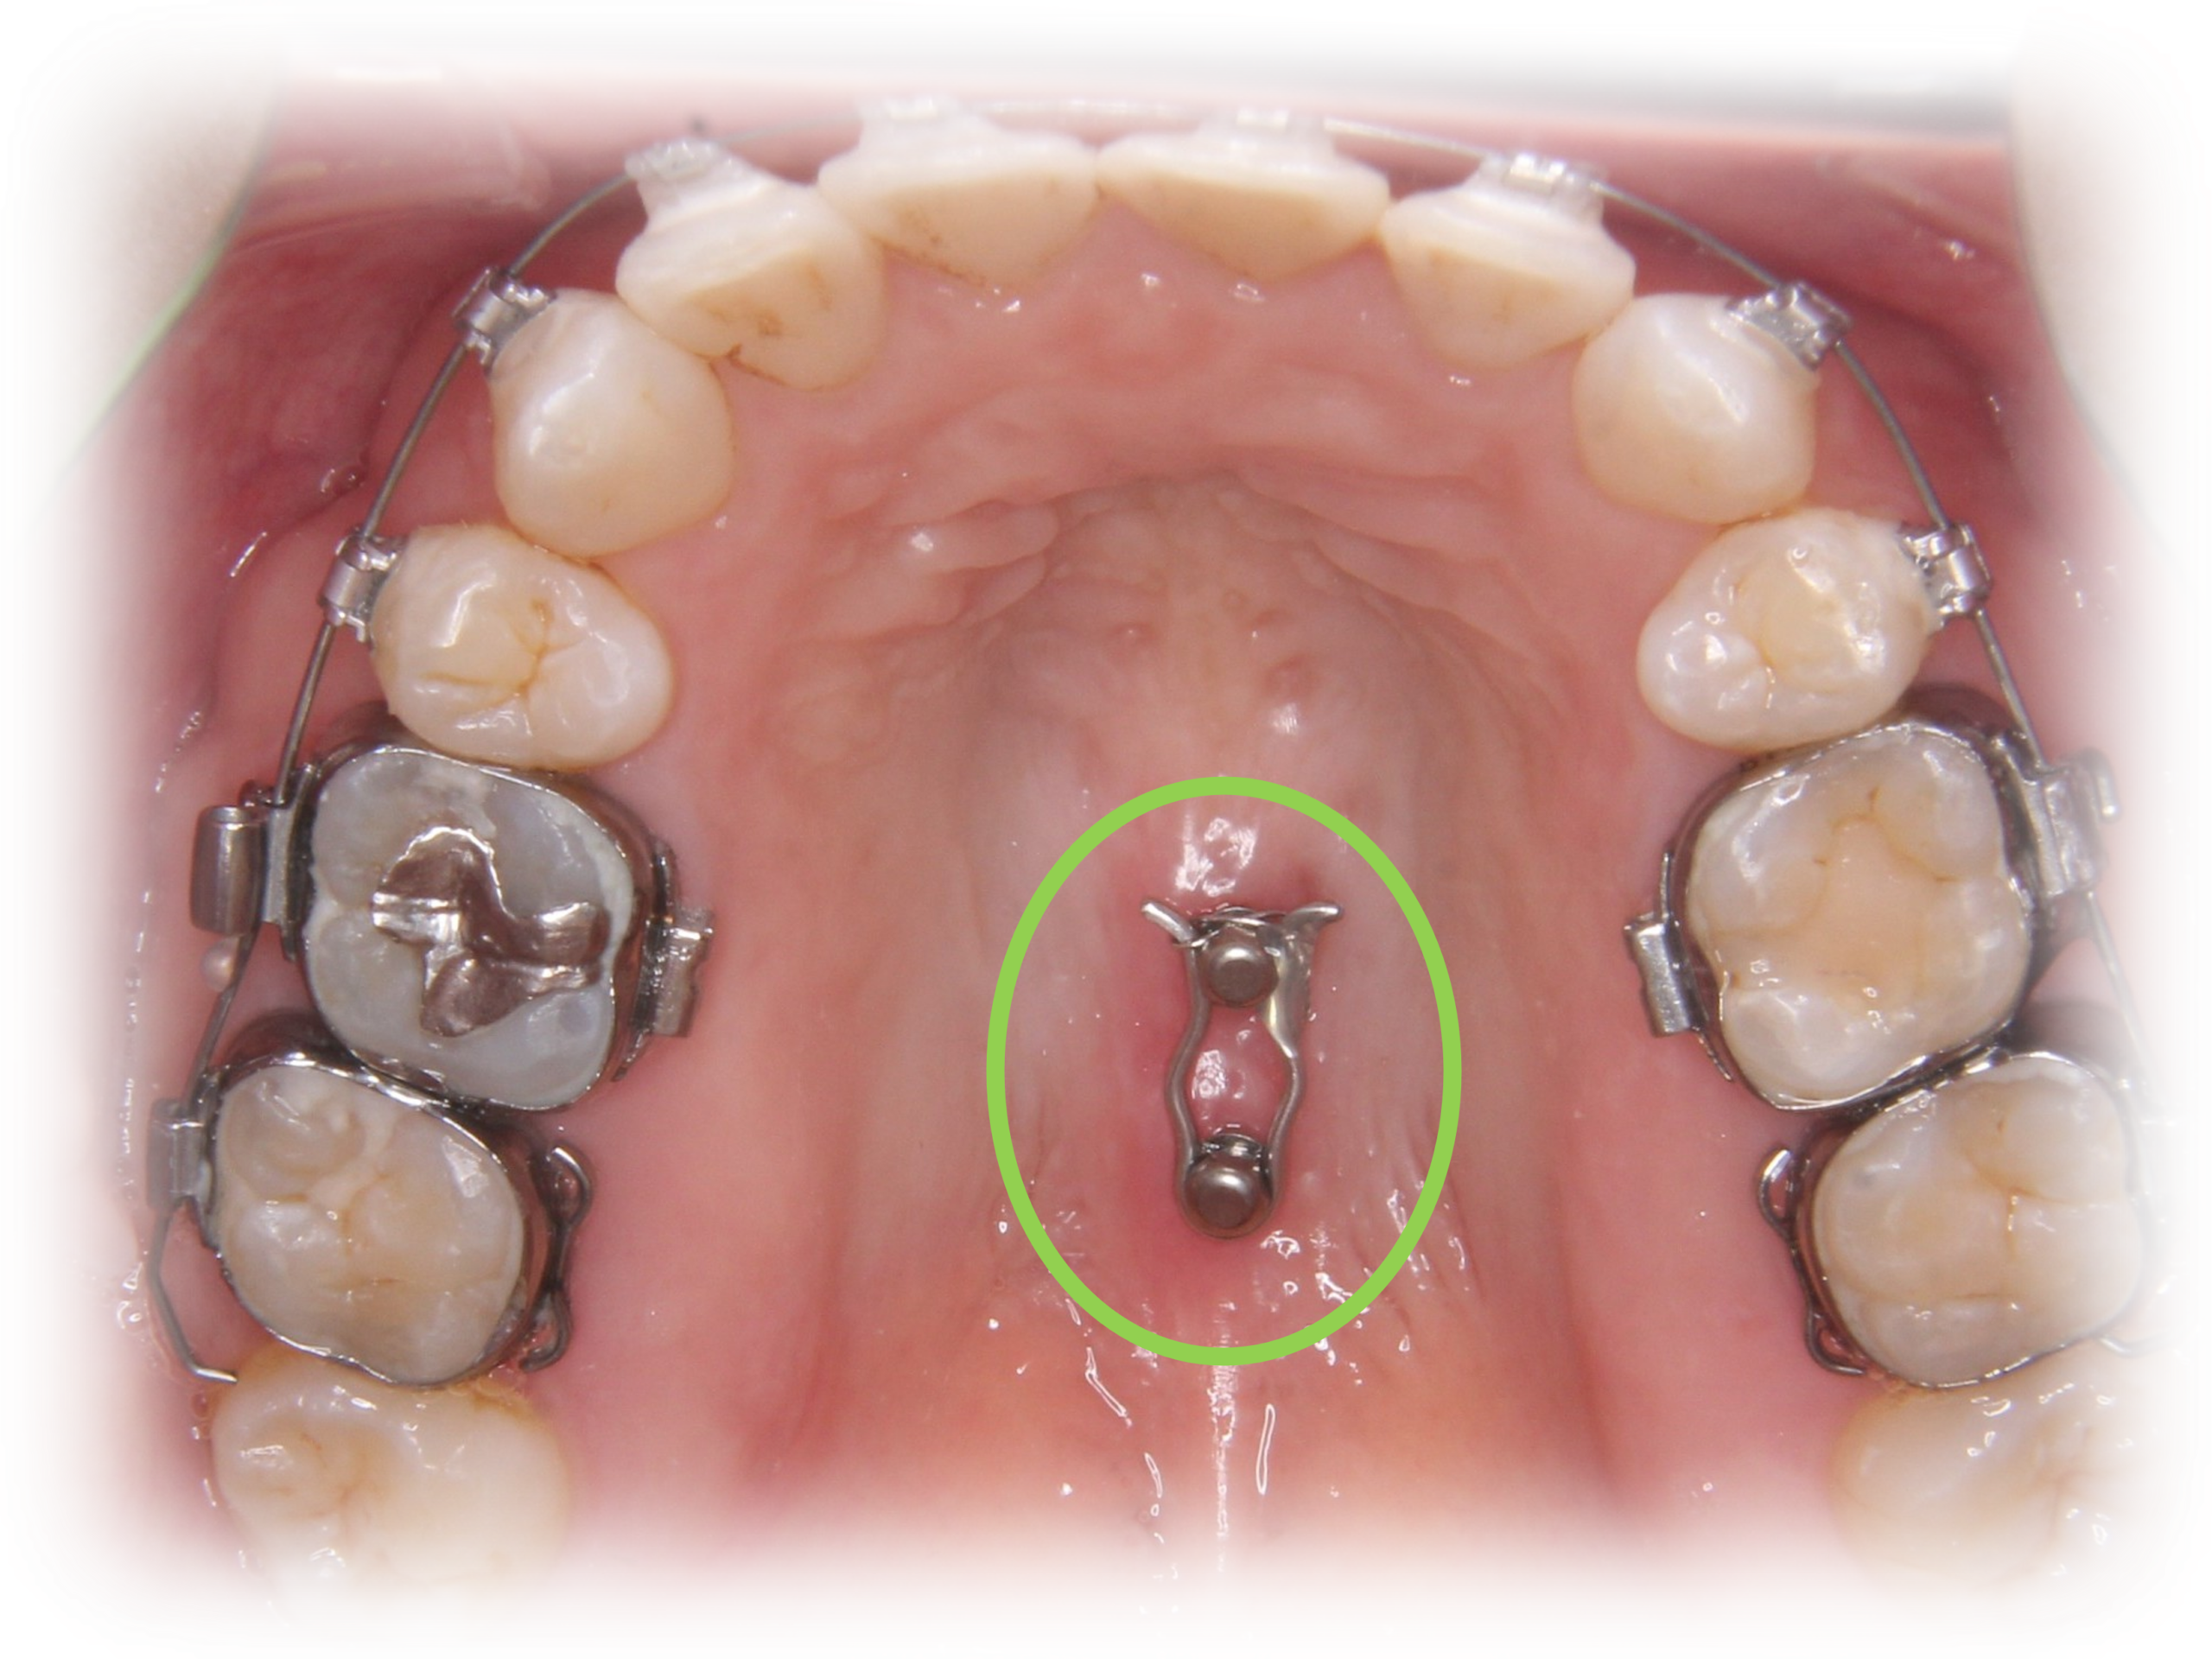

歯を効率よく動かすために、一時的に歯茎などに小さなネジ「アンカースクリュー」を装着する場合があります。

大きさは直径1.4〜2mm、長さ6〜10mm程でチタン合金という体に優しい素材を使用しています。